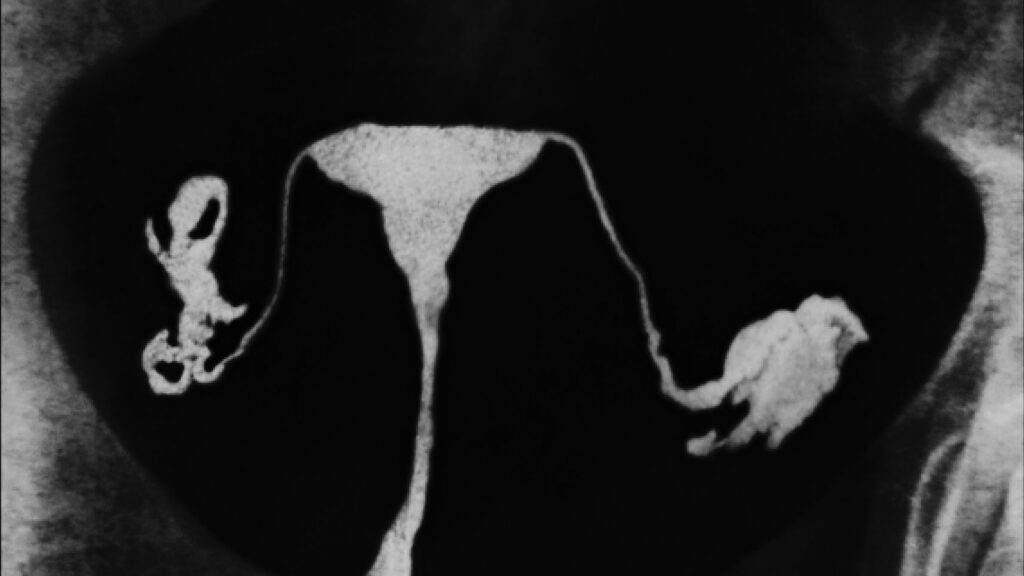

Increasing efforts to take out fallopian tubes to reduce ovarian cancer risk

Understanding Ovarian Cancer and Salpingectomy Rebecca Stone emphasizes that ovarian cancer often gets misidentified; in fact, the most prevalent form—responsible for the majority of cases and deaths—typically originates in the fallopian tubes, not the ovaries. This is not merely a trivia point; as a gynecologic oncologist at Johns Hopkins, Stone passionately advocates for greater awareness. […]